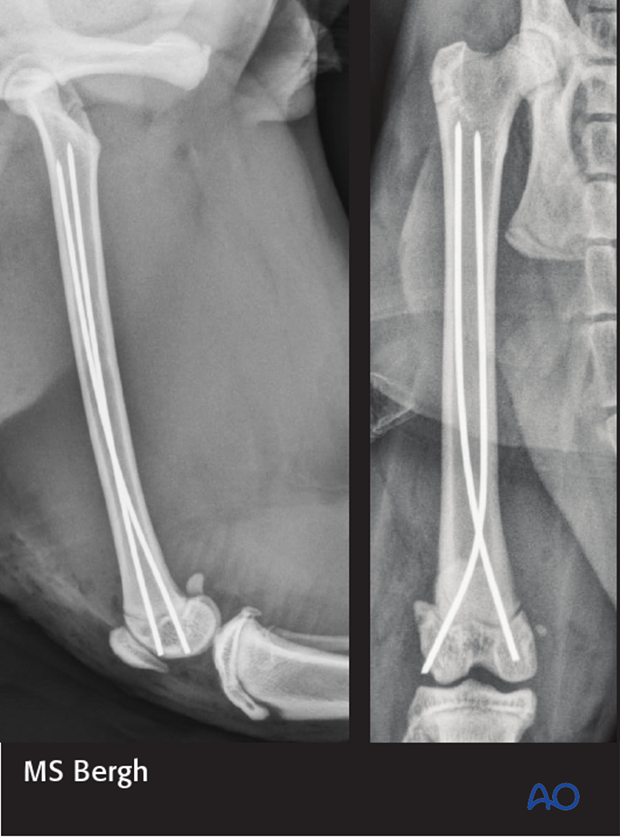

Radiographs show the modified Rush pinning/dynamic cross pinning technique in a cat with a Salter Harris 1 fracture of the distal femoral epiphysis.